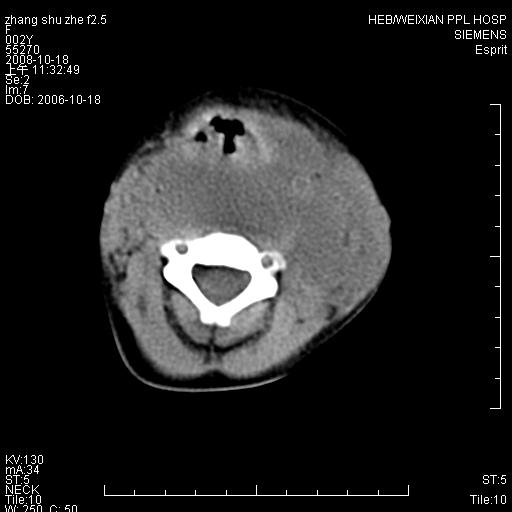

以下是引用dyqct在2009-2-10 21:04:00的发言:[br]年龄?性别?有发烧吗?[br]鼻咽部、口咽部、喉咽部及颈椎前间隙广泛肿厚,明显占位效应并致相应组织变形。ct值22-28hu。[br]考虑:1、颈前脓肿可能性大;[br] 2、建议增强或治疗后复查。

以下是引用jiangjing在2009-2-11 11:37:00的发言:[br]急性病程,鼻咽部、口咽部、喉咽部及颈椎前间隙广泛肿厚,明显占位效应并致相应组织变形.考虑颈部感染性病变(脓肿?);建议行进一步检查。